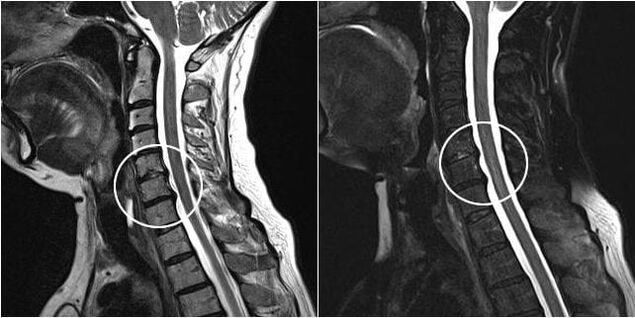

As the intervertebral discs and vertebrae deform, the patient's condition worsens.The course of osteochondrosis is complicated by neurogenic symptoms caused by compression by osteophytes or hernial protrusion of spinal roots and vertebral artery.Headache, dizziness, changes in blood pressure appear, and the sharpness of vision and hearing decreases.

Indications for surgical intervention include ineffectiveness of conservative treatment, as well as complications of cervical osteochondrosis, for example, discogenic myelopathy, vertebral artery syndrome and radicular syndrome.The following operations are performed to decompress the spinal cord, blood vessels and spinal roots: